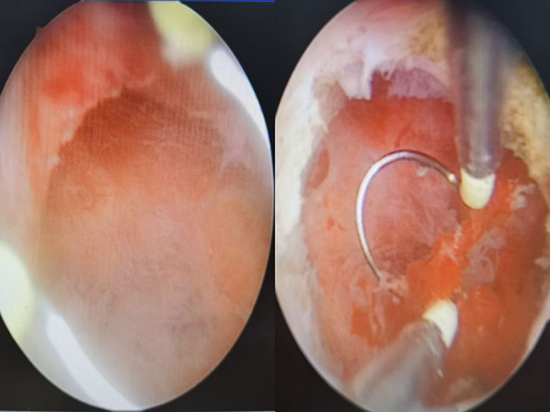

此次手术由妇产科白帆副主任医师主刀,洪雪玲主治医师协助。由于该手术涉及宫内电操作,且憩室顶部残余肌层薄,紧邻膀胱,憩室空间狭小(10mm3左右),操作稍有疏忽,即可造成子宫穿孔、膀胱损伤。所以要求手术者经验非常丰富,操作极为精准,电切、电凝要恰到好处,属于4级高风险手术,可谓“螺狮壳里做道场”。

参与手术的医护人员凭借着丰富的经验和高超的技术,顺利进行各种精细化操作:在宫腔镜直视下电切纤维活瓣组织,使经血可以顺利流出;用电凝球电凝暴露的小血管及憩室内膜,减少经期憩室内膜出血……最终手术成功完成,患者术后症状改善,情况良好。